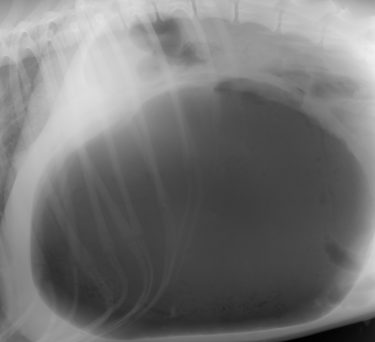

問診の時点で胃拡張・捻転症候群が強く疑われたため、診断のためのレントゲン検査を行った。

胃は非常に重度に拡張・捻転しており、呼吸も弱くなっていた。

緊急対応として胃を穿刺し、抜気した。

抜気後、やや胃が縮小した